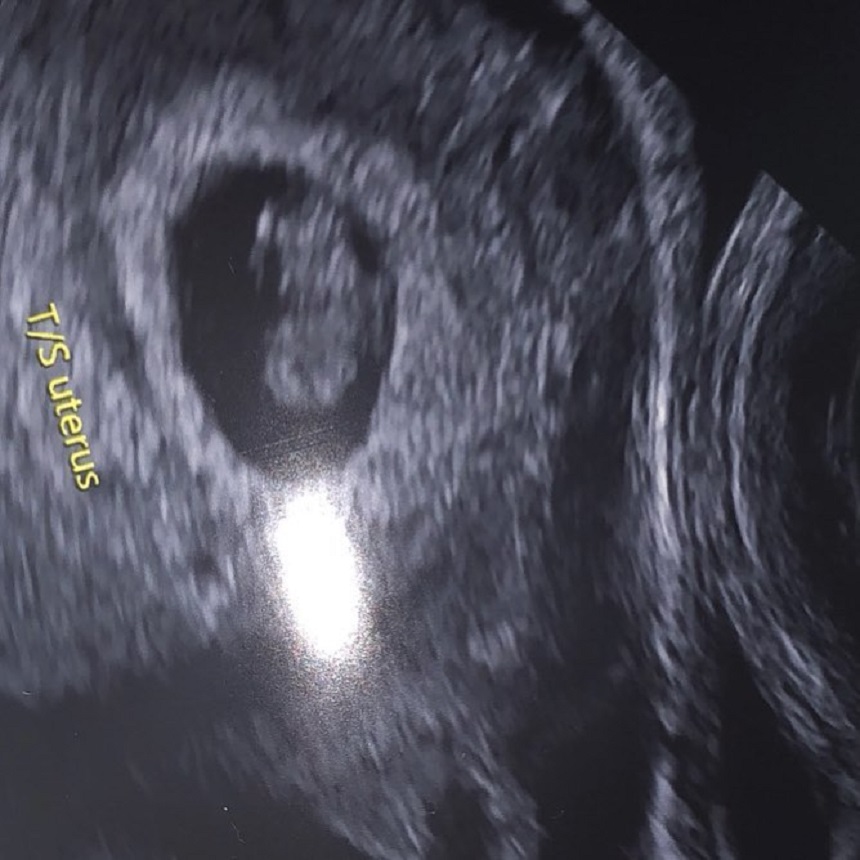

Malin Andersson a confirmat, la începutul lunii iunie, că așteptă un copil cu Tom Kemp, cu care are o relaţie de aproximativ opt luni de zile. Recent, bruneta a făcut publică o fotografie cu prima ecografie a bebeluşului ei, alintându-l ca fiind un ''mic caju''.